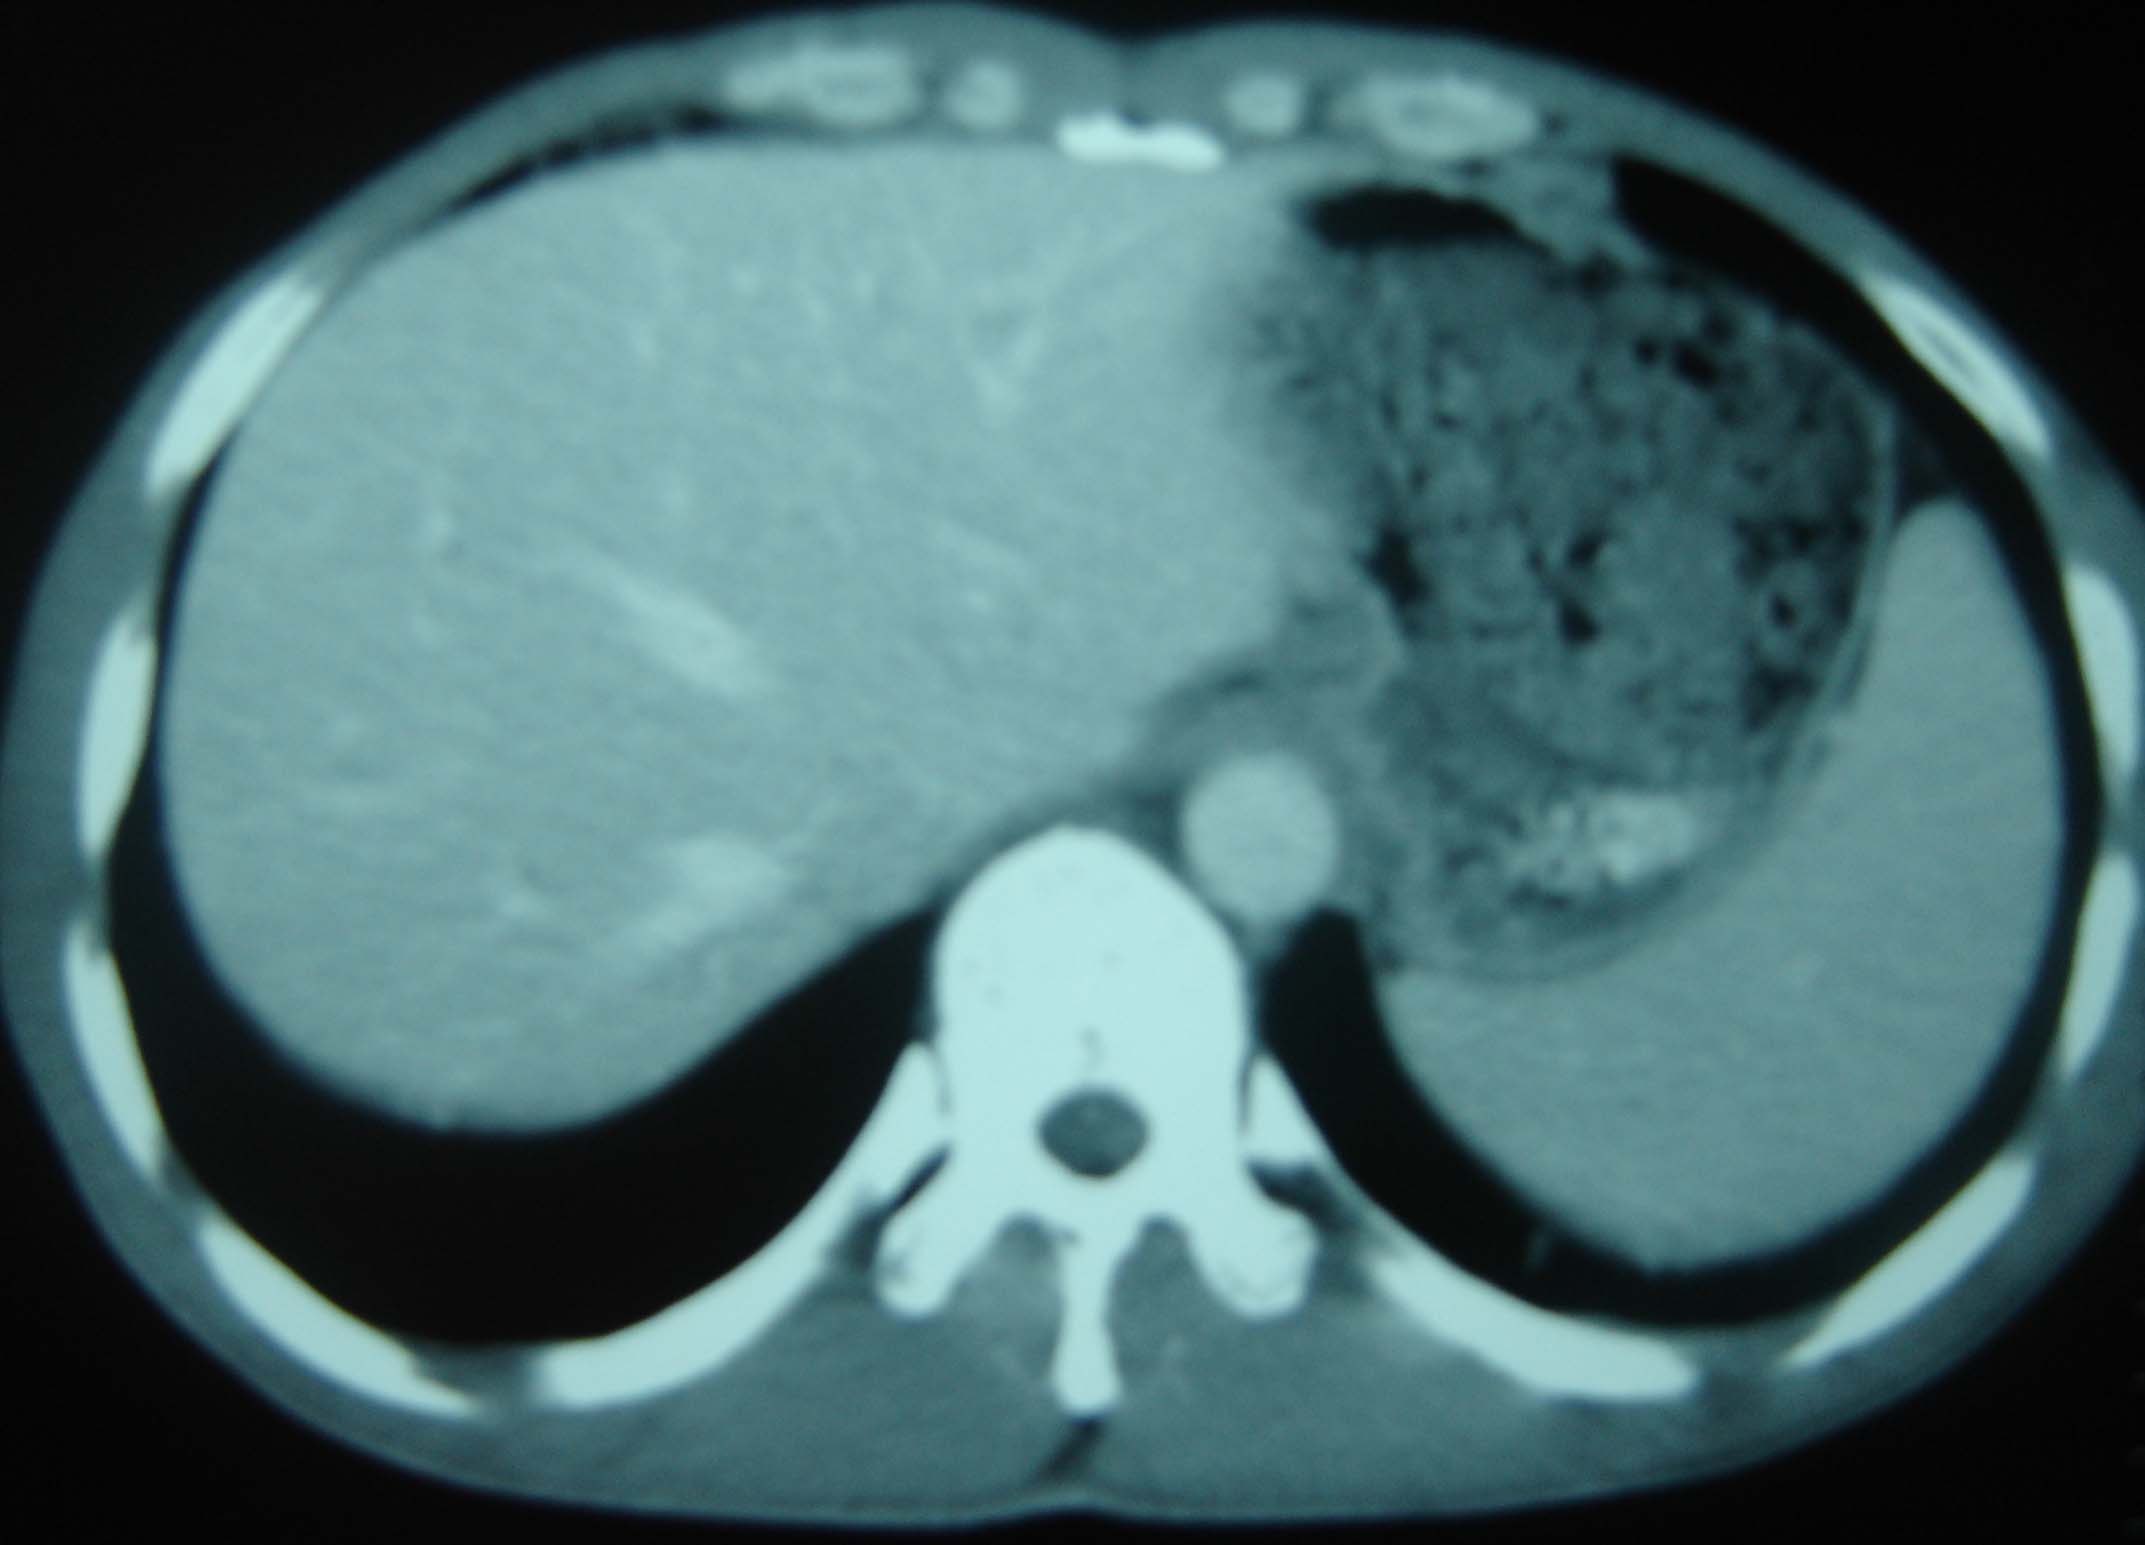

男 、43岁,咳嗽胸痛,装修工,平时接触粉尘较多,有吸烟史10多年,纤维支气管镜检查未发现异常,胃镜、腹部b超检查亦未发现异常,颈部淋巴结活检未发现肿瘤细胞。

1)考虑双肺及胸膜多发性转移瘤。2)肺气肿。